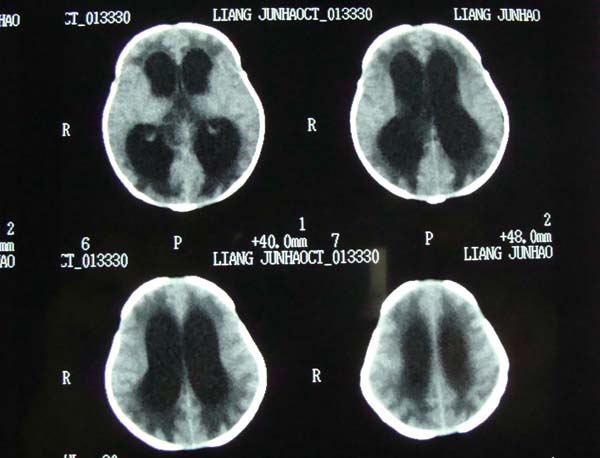

病史,xxx,男,10个月,前囟饱满.呕吐.

考虑第四脑室室管膜瘤并阻塞性脑积水。

小脑蚓部髓母细胞瘤?第四脑室室管膜瘤?合并重度阻塞性脑积水。

考虑第四脑室室管膜瘤并阻塞性脑积水

考虑第四脑室室管膜瘤或髓母细胞瘤并阻塞性脑积水。

诊断:髓母细胞瘤并梗阻性脑积水.

依椐:颅后窝中线小脑蚓部占位,病灶内呈混杂密度,四脑室受压前移,第三脑室及侧脑室扩张.